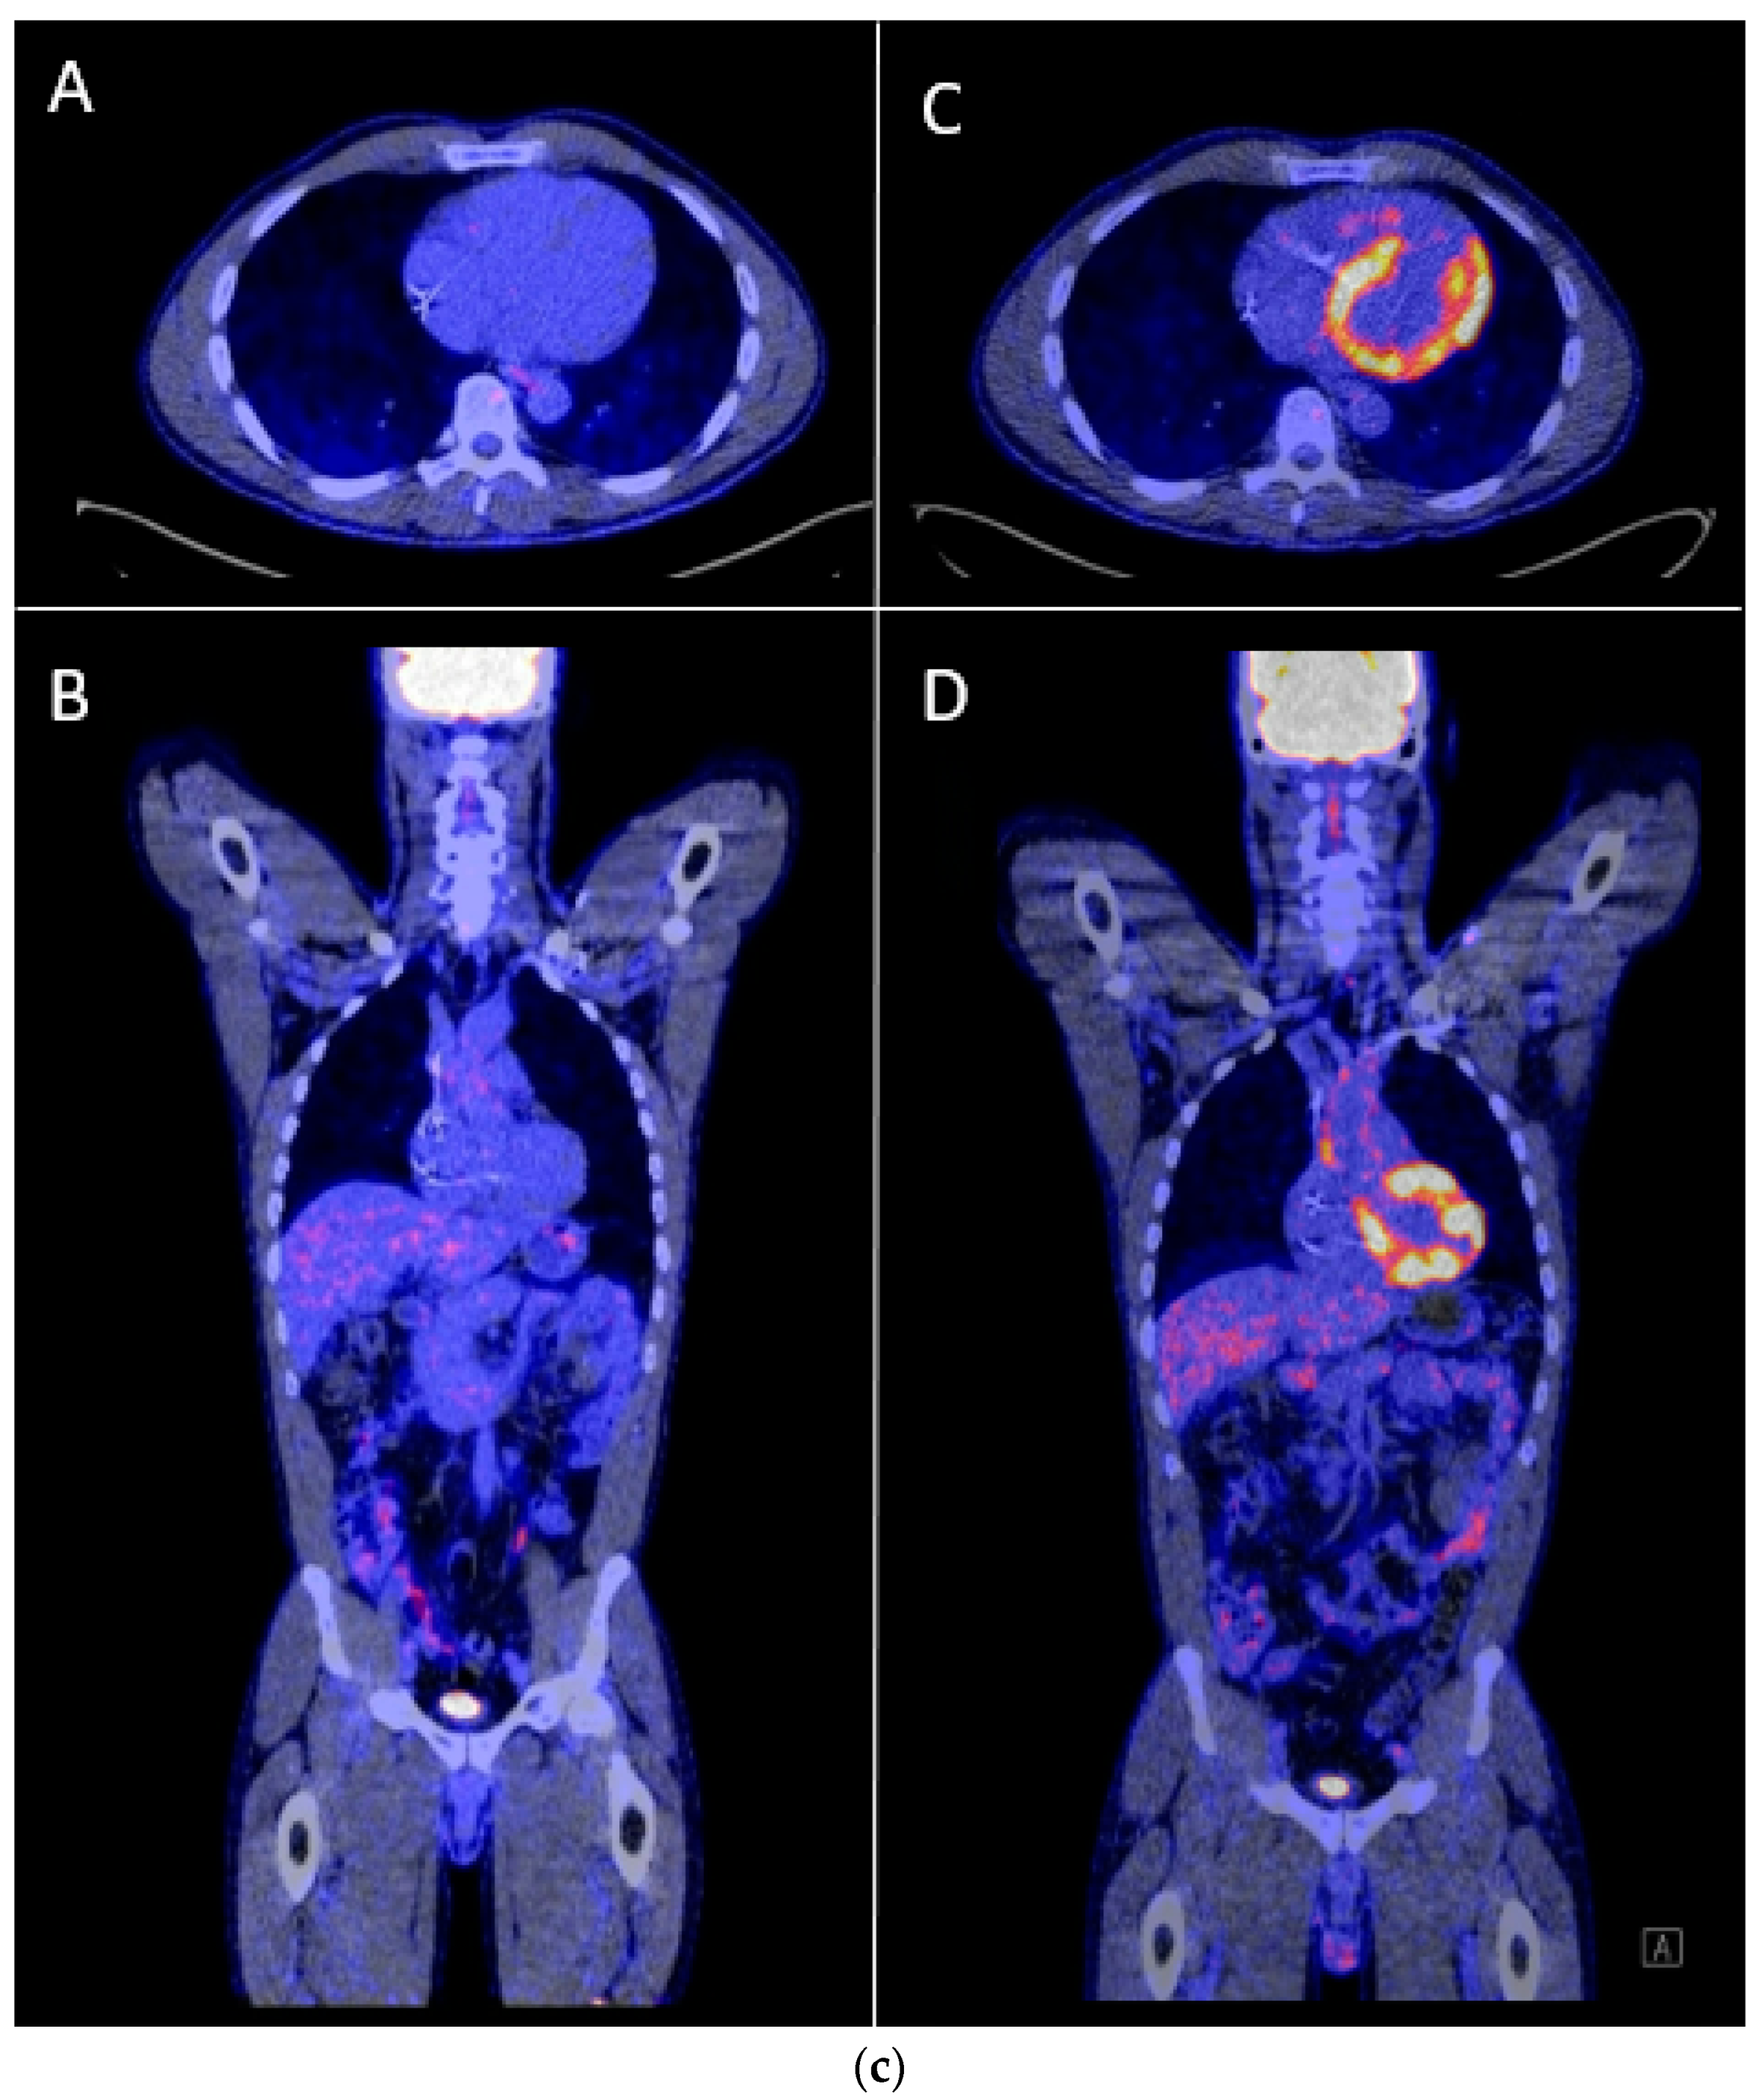

| Patient activity | Heart failure [25] and severe anemia (this review). |